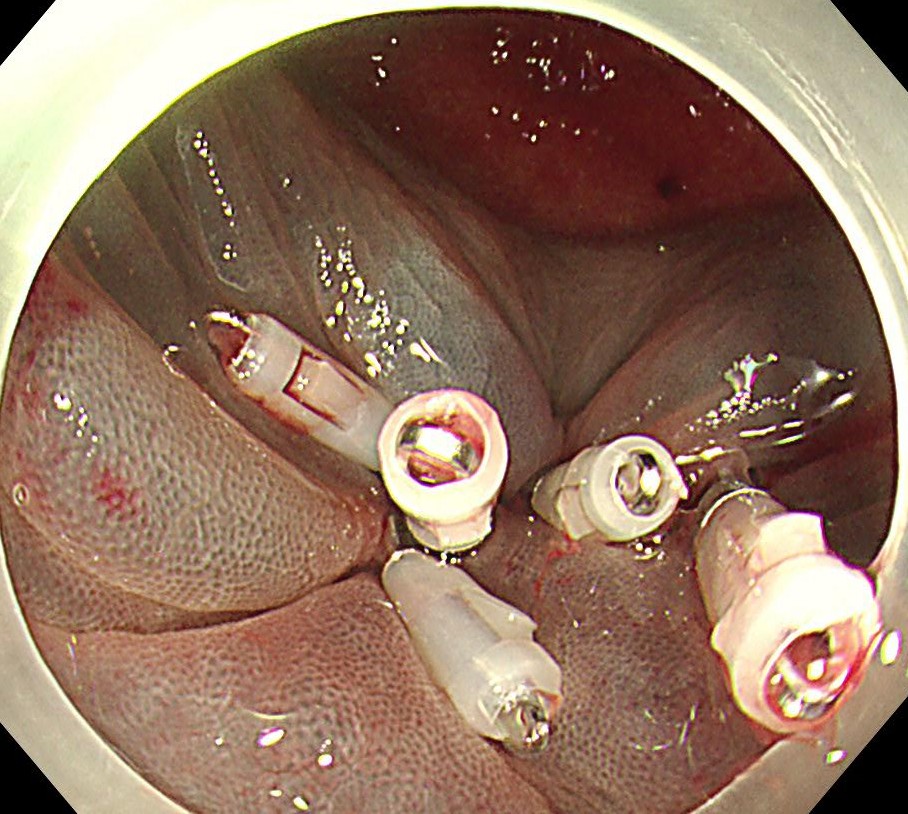

前後左右にスネアキーとなるよう粘膜切開を置き、内視鏡的一括切除 (EMR) しました。